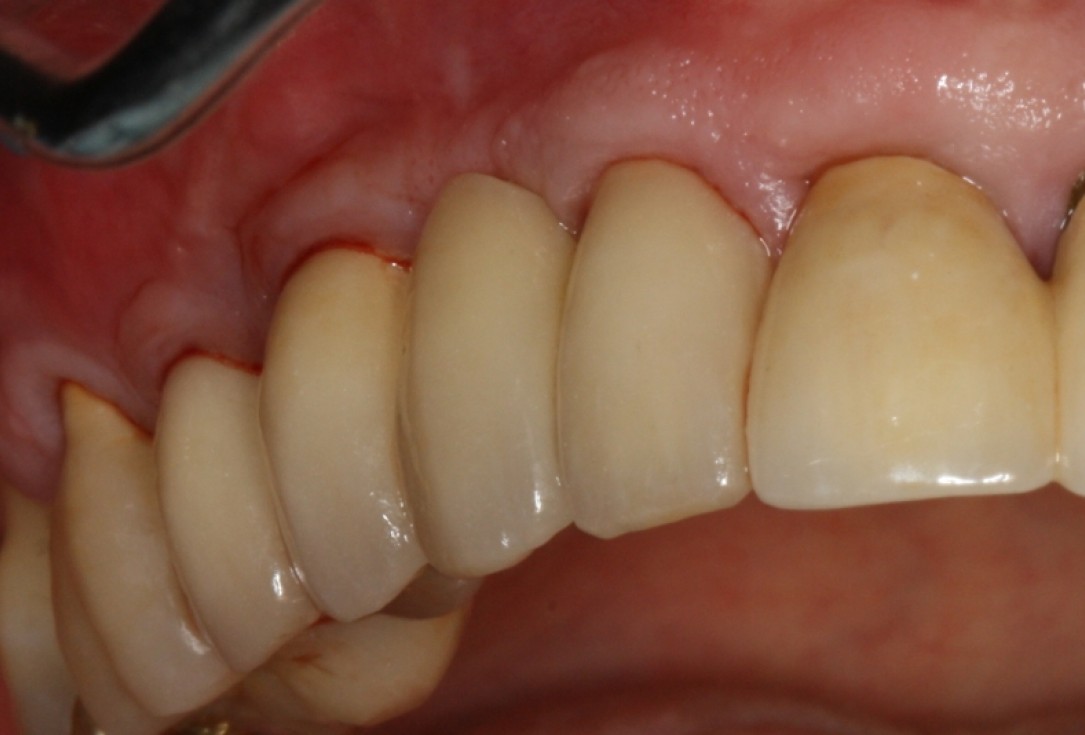

Clinical situation with narrow alveolar ridge in the lower jaw